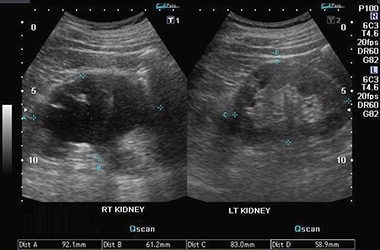

| Ультразвуковое исследование | УЗИ позволяет четко увидеть увеличение почек, а также диагностировать патологии соседних органов, способствующие развитию гидронефроза |